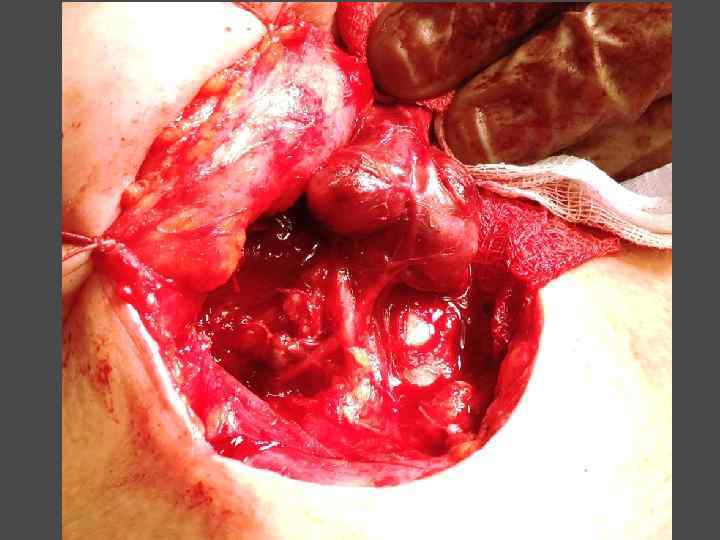

ХИРУРГИЧЕСКОЕ ЛЕЧЕНИЕ ЗОБА

ХИРУРГИЧЕСКОЕ ЛЕЧЕНИЕ ЗОБА

ОСЛОЖНЕНИЯ ХИРУРГИЧЕСКОГО ЛЕЧЕНИЯ ►Поражение возвратного нерва, приводящее к параличу голосовой связки на стороне поражения, как следствие – изменение тембра голоса, сужение голосовой щели, затруднение дыхания. ► Кровотечение. ►Тиреотоксический криз. ► Гипопаратиреоз. ► Рецидив тиреотоксикоза. ► Формирование порочного рубца.

ЭКТОПИРОВАННАЯ В ТИМУС ПАРАЩИТОВИДНАЯ ЖЕЛЕЗА